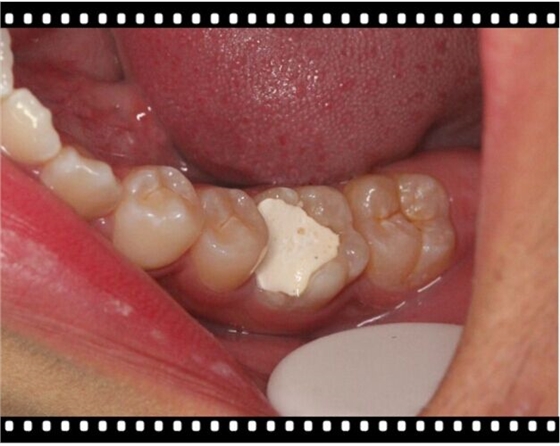

以下病例大部分是以Kerr的低端Neofil通用樹(shù)脂修復(fù)(基本都是粗拋紅標(biāo)車針),修復(fù)調(diào)合后即刻照。